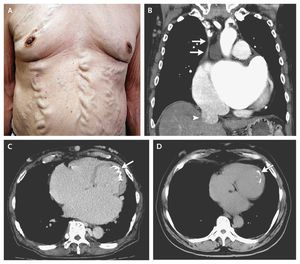

A 68-year-old man who had Behçet's disease with a 30-year history of oral and genital ulcers and erythema nodosum presented with progressive leg edema and dyspnea. The physical examination revealed varices of the chest and abdominal wall (Panel A), caused by collateral circulation associated with obstruction of the superior vena cava (SVC). Chest computed tomography (CT) showed SVC obstruction (Panel B, arrows) and dilatation of the inferior vena cava (arrowhead). Endocardial calcification on the midlateral and apical wall (Panel C, arrow) was more extensive than that seen on imaging performed 11 years earlier (Panel D, arrow), and there was increased dilatation of the right ventricle and both atria. A restrictive cardiomyopathy with endomyocardial fibrosis, which can be a complication of Behçet's disease, was diagnosed on the basis of echocardiography (video) and cardiac catheterization (including endomyocardial biopsy). After diuresis, the edema and dyspnea improved, but the varices of the trunk and lower limbs remained. Takafumi Nishida, M.D. Daihiko Hakuno, M.D., Ph.D. National Defense Medical College, Saitama, Japan source: nejm.org